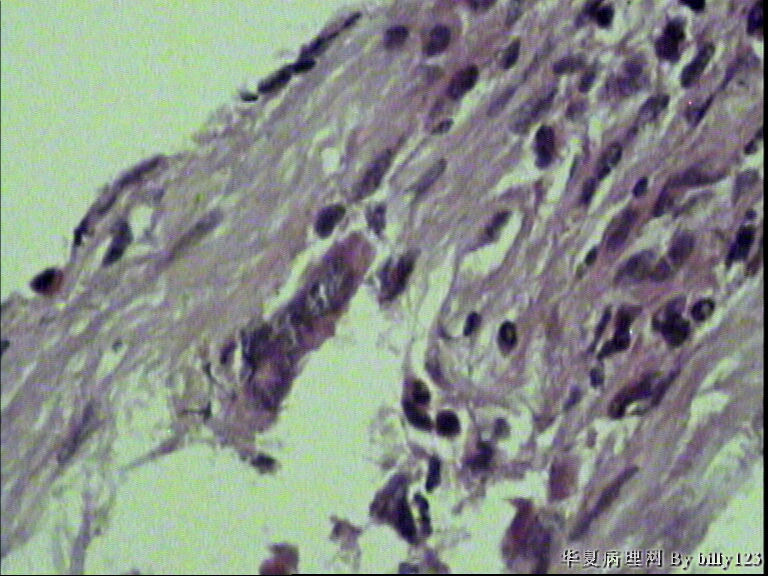

纤支镜活检,女性,75岁,请各位老师指教!

图2